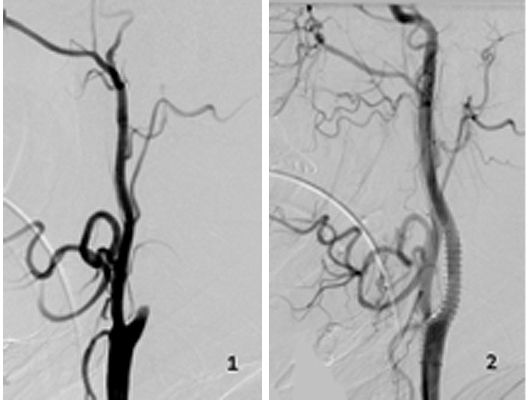

Angiographie: Rekanalisierende Verfahren

Rekanalisierende Verfahren (Wiedereröffnung von Blutgefäßen)

Mit den modernen Verfahren zur Wiedereröffnung von verschlossenen Blutgefäßen können wir Patienten mit Schlaganfall in vielen Fällen helfen. Das folgende Beispiel zeigt die angiographischen Bilder eines Patienten, der mit vollständiger Lähmung der rechten Körperhälfte und einer schweren Sprachstörung eingeliefert wurde. Ursächlich zeigte sich ein Verschluss der linken Halsschlagader, vermutlich auf dem Boden einer arteriosklerotischen Einengung (Bild 1). Das Gefäß wurde daraufhin mit einem Stent wiedereröffnet (Bild 2). Zusätzlich zeigte sich ein Verschluss der Endstrecke des Gefäßes durch Blutgerinnsel (Bild 3). Diese konnten vollständig entfernt werden (Bild 4). Der Patient erholte sich nach der Behandlung innerhalb weniger Tage vollständig.